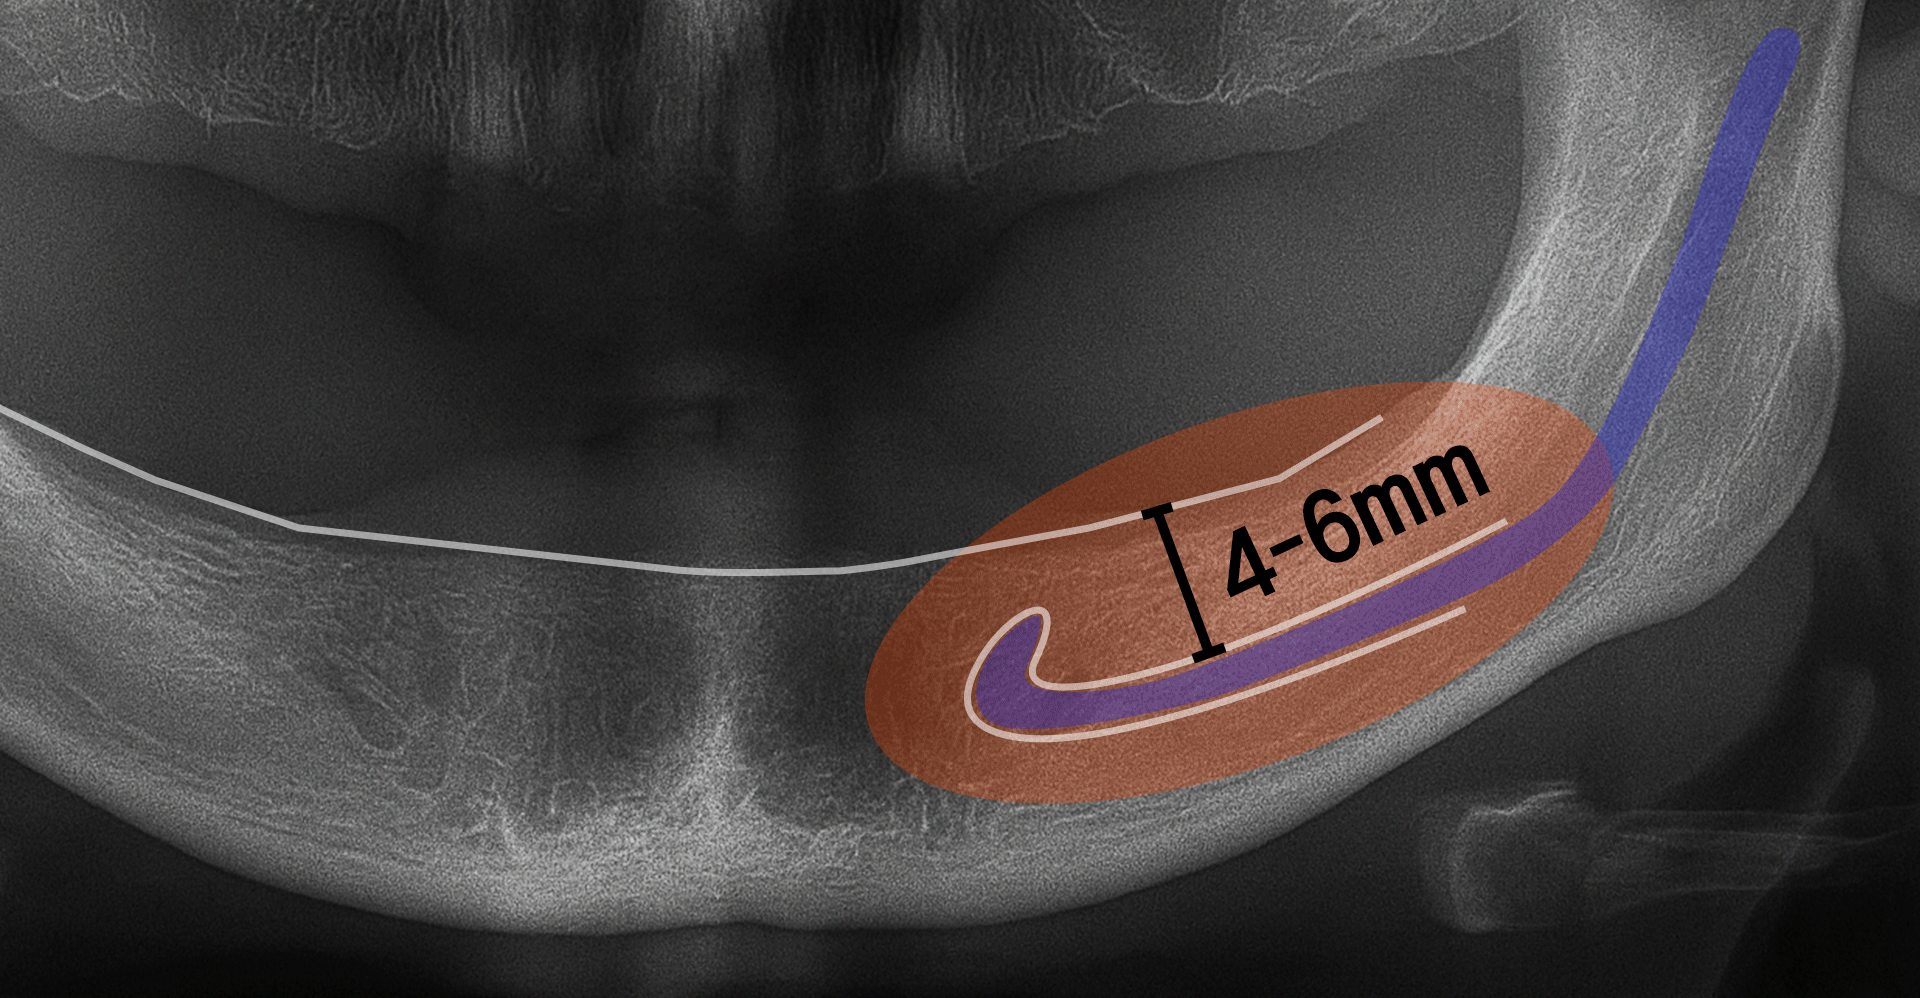

결론부터 말씀 드리면, 잇몸뼈(잔존골)가 충분히 남아 있어야 임플란트 식립이 가능하며, 일반적으로 상악과 하악 모두 최소 4~6mm 이상의 골 높이와 적절한 골 폭이 확보되어야 합니다.

- 4~6mm: 측방 접근법 → 잇몸 옆쪽에 창을 내고 공간 확보

- 4mm 미만: 측방 접근 + 대규모 뼈이식 → 뼈가 거의 없어 큰 보강 필요